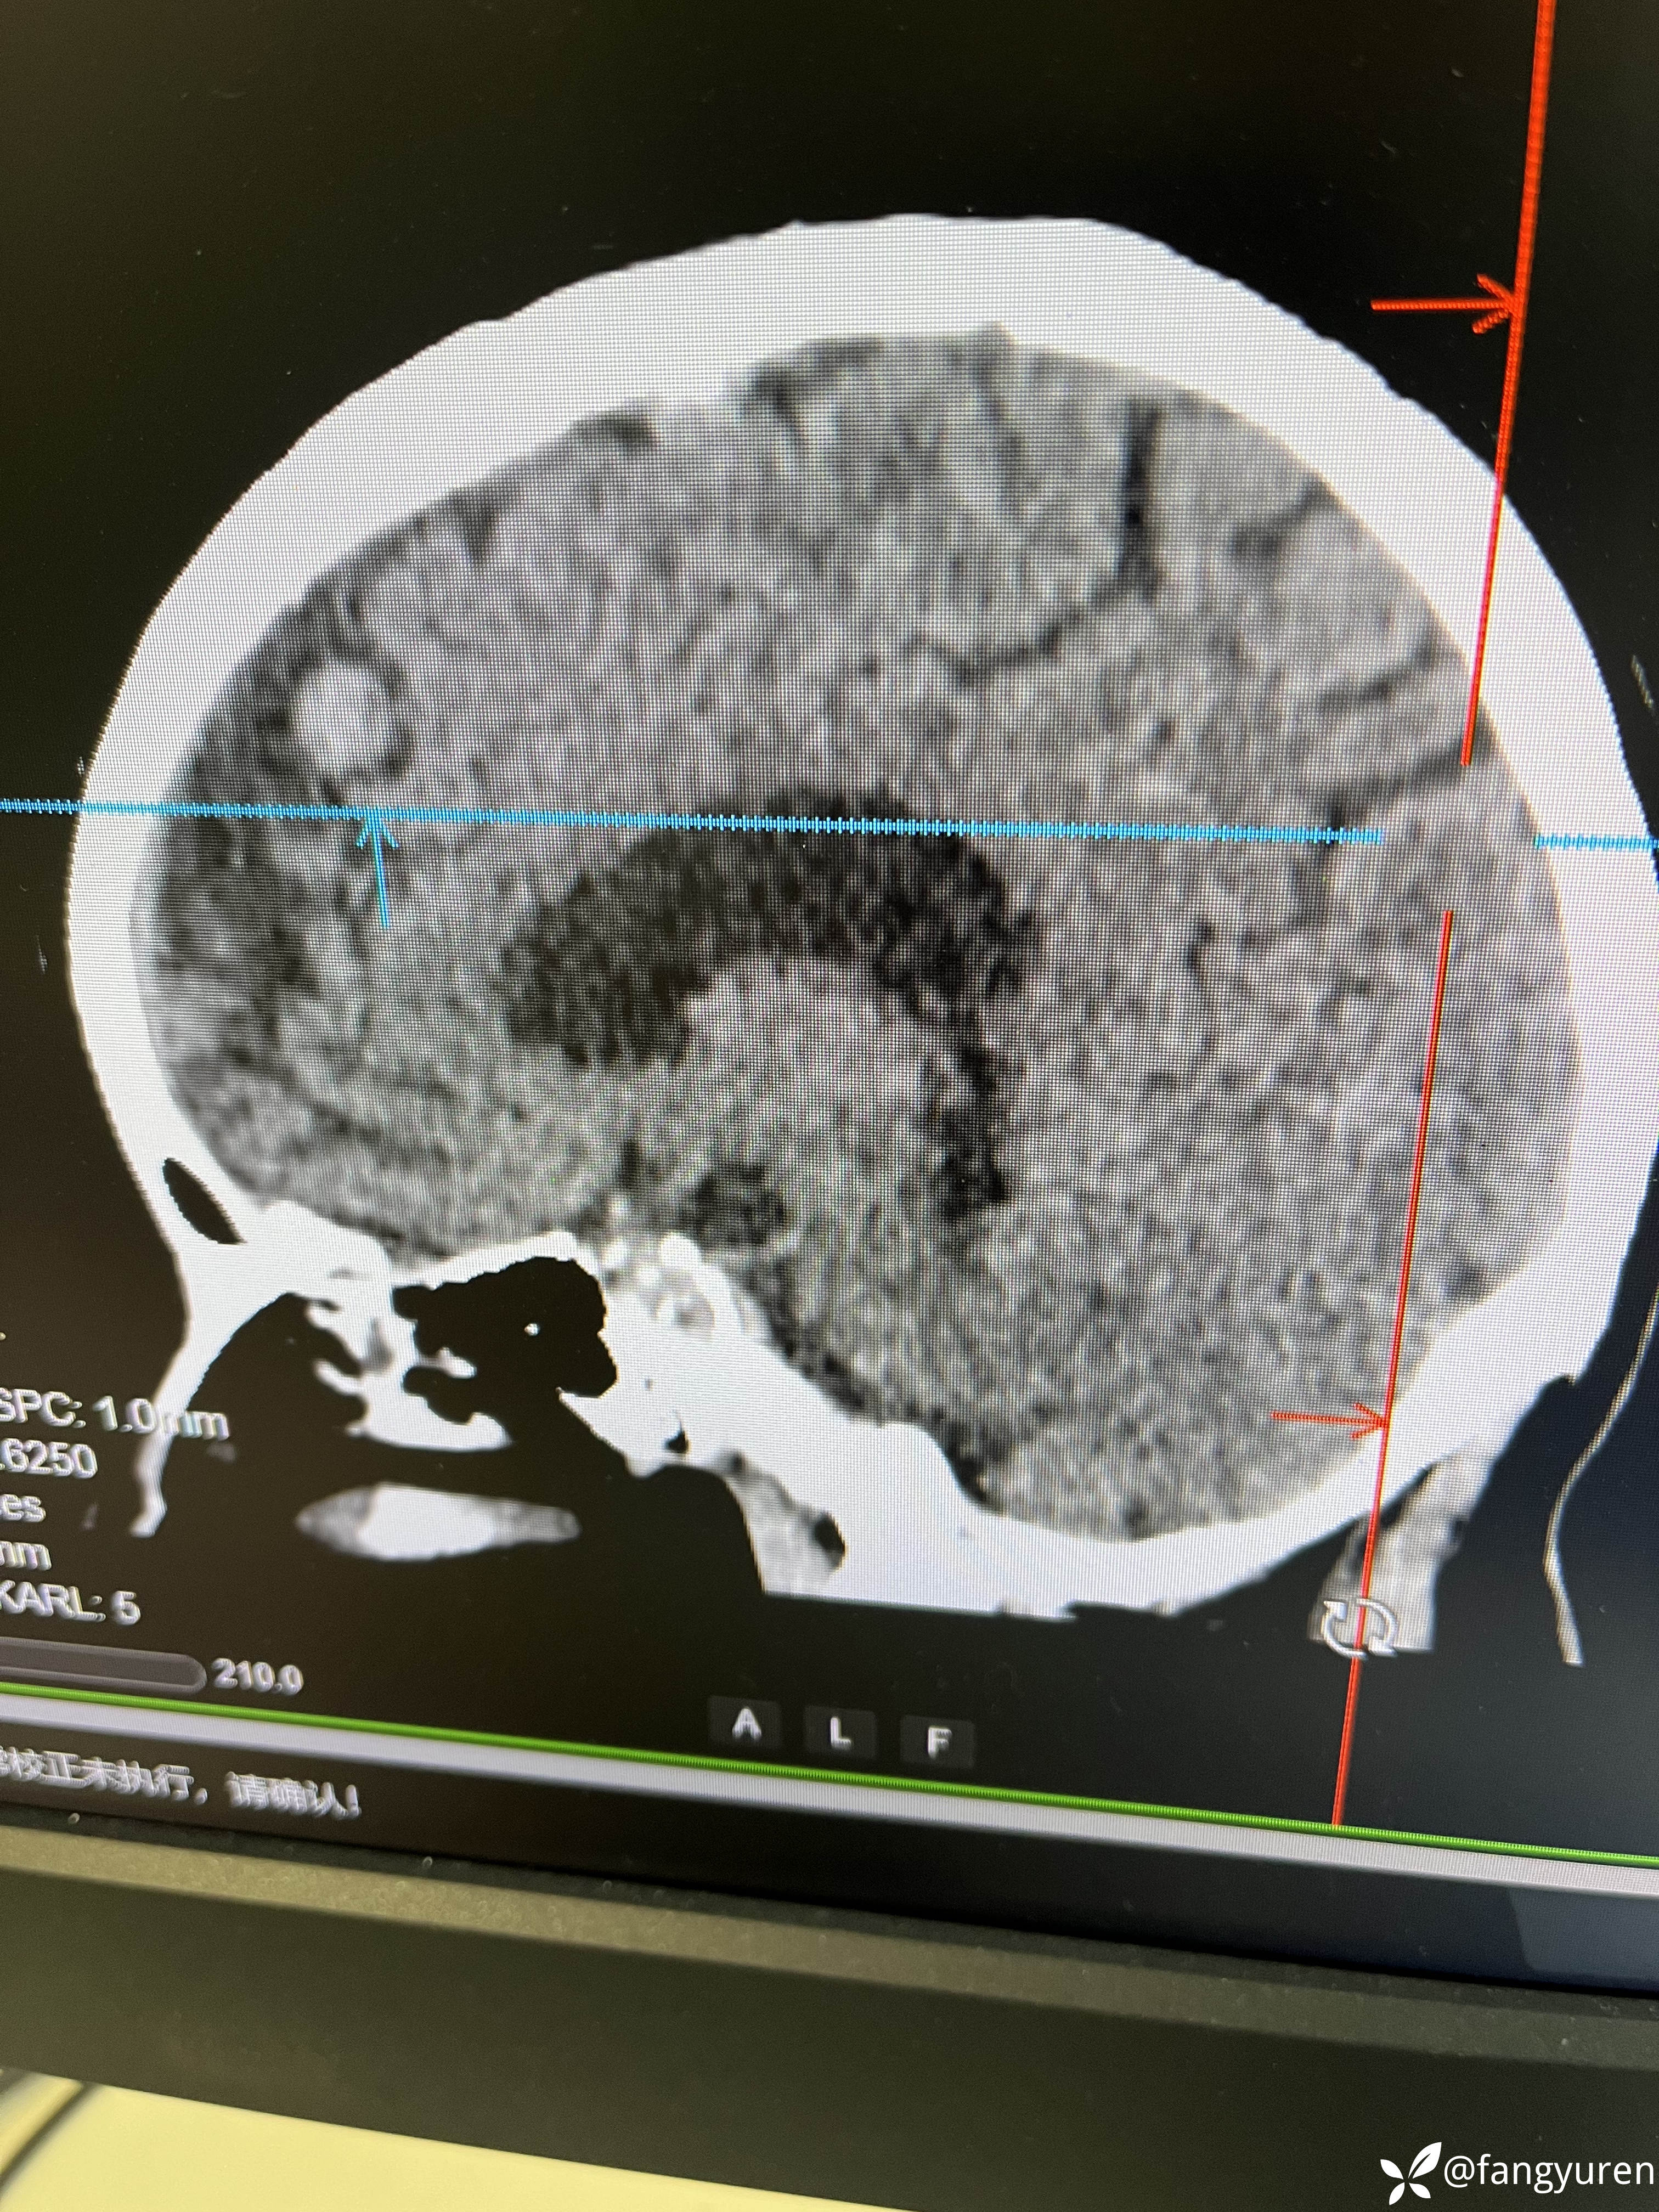

女66,头晕来摄影,发现大脑左侧纵裂旁、左侧额部颅骨下和右侧侧脑室后角见多发类圆形稍高、等、低密度影,部门钙化提示脑膜瘤。如图,蓝圈圈(详细请看视频)所示右侧侧脑室后角见类圆形低密度,周边钙化,考虑是什么,囊状脑膜瘤?多谢老师